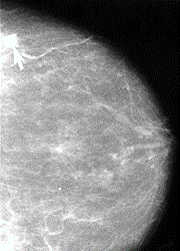

One of the most used tests is a screening mammogram. A mammogram is a low-dose x-ray. The x-ray picture shows your breast tissue including any abnormal areas. Mammograms cannot show if an abnormal area is cancer, but they can help your healthcare provider decide if you need more tests. You can only get a screening mammogram before you have symptoms. Once you have any symptoms you will need a diagnostic test.

Healthcare providers use a standard system called Breast Imaging Reporting and Data System (BI-RADS) to describe mammogram results. The results are a numbered category from 0-6.

- 0- Incomplete: Additional imaging is needed

- 1- Negative: Normal result, nothing new or abnormal was found

- 2- Benign finding: No sign of cancer, but there was a non-cancerous finding

- 3- Probably benign finding: Low chance of being cancer, but you will likely need more imaging tests

- 4- Suspicious abnormality: May be cancer, breast biopsy recommended

- 5- Highly suggestive of malignancy: High chance of being cancer, breast biopsy strongly recommended

- 6- Known biopsy-proven malignancy: Previous biopsy has already shown cancer

Your mammogram report will also have information about your breast density, which is how much other tissue is in your breast compared to fatty tissue. Denser breasts make it harder to see abnormal areas on mammograms. It also slightly raises your risk of breast cancer.